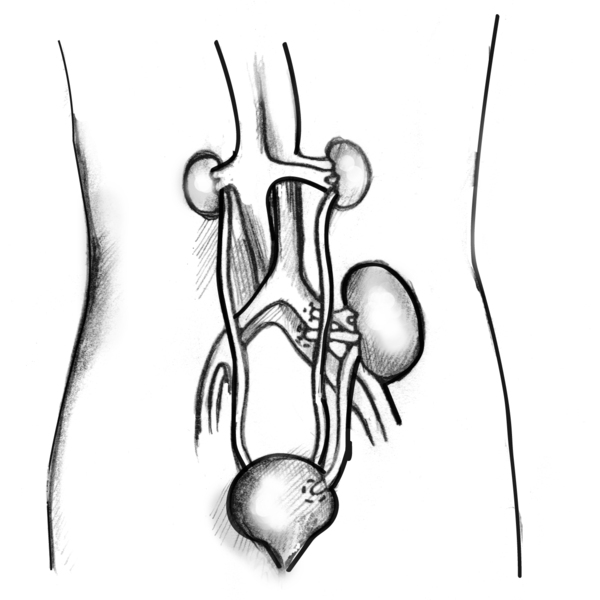

Anatomical diagram of a female figure with a transplanted kidney. The two diseased kidneys are still in place on either side of the spine, just below the rib cage. The Picture of a transplanted kidney inside an outline of the abdomen. The two damaged kidneys are still in place on either side of the spine, just below the rib cage. The transplanted kidney is located on the left side, just above the bladder. A transplanted ureter connects the new kidney to the bladder. Labels point to the damaged kidneys, transplanted kidney, bladder, and transplanted ureter.

Anatomical diagram of a female figure with a transplanted kidney. The two diseased kidneys are still in place on either side of the spine, just below the rib cage. The Picture of a transplanted kidney inside an outline of the abdomen. The two damaged kidneys are still in place on either side of the spine, just below the rib cage. The transplanted kidney is located on the left side, just above the bladder. A transplanted ureter connects the new kidney to the bladder. Labels point to the damaged kidneys, transplanted kidney, bladder, and transplanted ureter.

Anatomical diagram of a female figure with a transplanted kidney. The two diseased kidneys are still in place on either side of the spine, just below the rib cage. The Picture of a transplanted kidney inside an outline of the abdomen. The two damaged kidneys are still in place on either side of the spine, just below the rib cage. The transplanted kidney is located on the left side, just above the bladder. A transplanted ureter connects the new kidney to the bladder. Labels point to the damaged kidneys, transplanted kidney, bladder, and transplanted ureter.